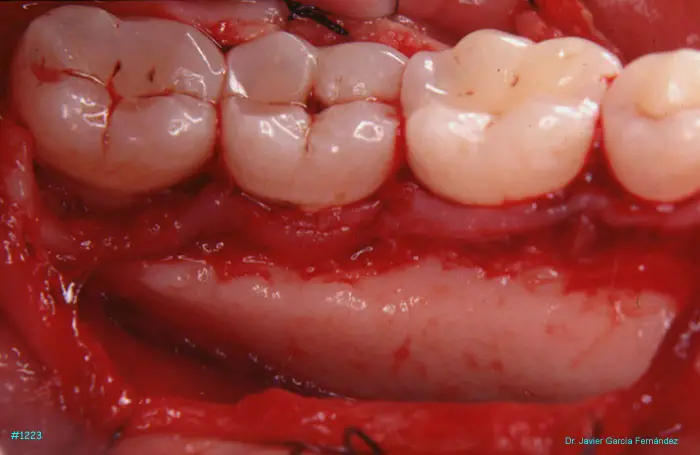

Atlas of Surgical Techniques in Periodontics. Chapter III. Atlas de Técnicas Quirúrgicas en Periodoncia